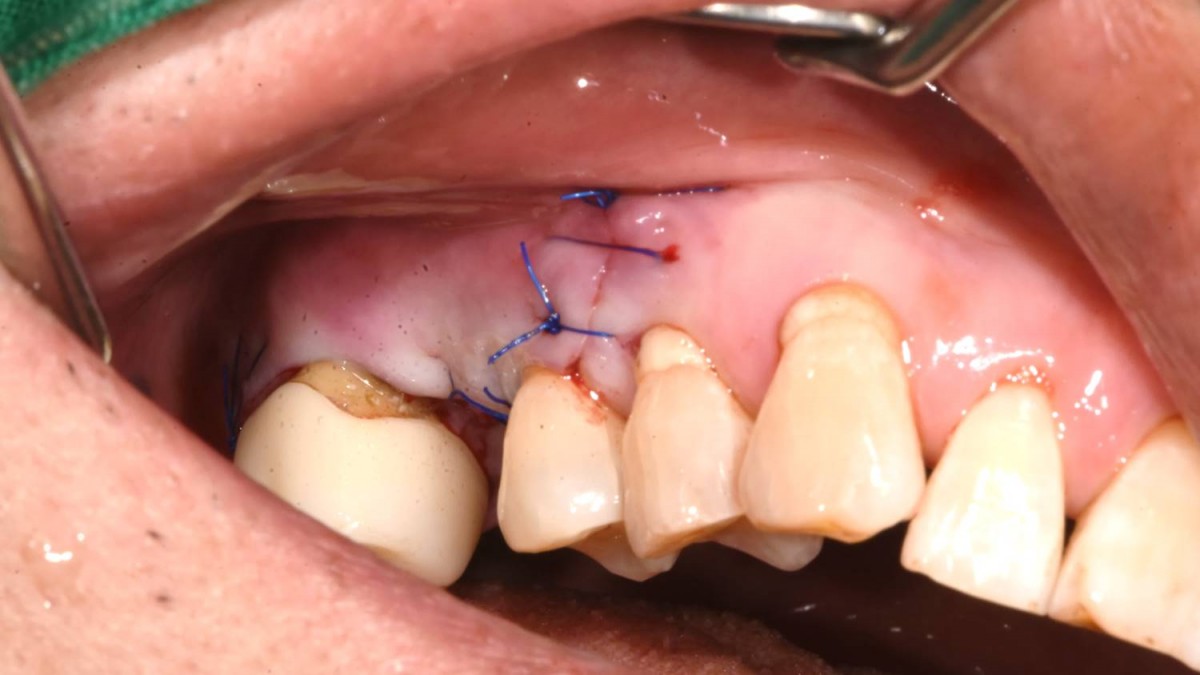

Maxillary Sinus Graft, 2 Implants, Crown Contouring

<GCaks> A 56-year-old male patient had pain-inducing caries, and perio-involved tooth mobility resulted in a tooth fracture at 1st molar. And it was removed months ago. He was a heavy smoker and showed poor oral hygiene.